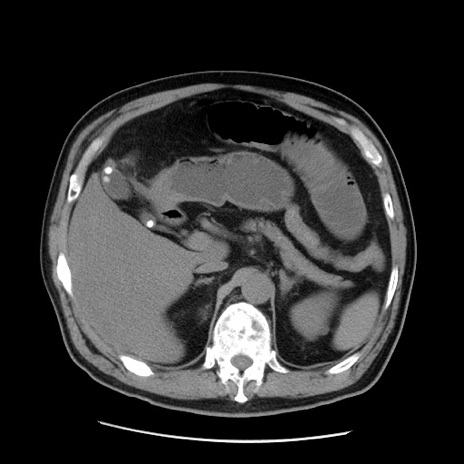

症例20(横断像)

【症例】 60歳代男性

【主訴】 腹部膨満、嘔吐

【現病歴】5日前頃より倦怠感を認め食事量減少し4日前の朝嘔吐、食事摂取困難となった。 3日前近医受診し点滴施行され整腸剤などを処方された。 当日他院を受診し、腹部膨満著明、炎症反応の上昇(CRP10.8、WBC11200)あり、紹介受診となる。

【身体所見】 意識JCS1 受け答えがはっきりしないBP 111/57mHg、 P 67bpm、、BT35.2°C、SpO2 97%(RA)、 腹部:膨隆、打診で鼓音あり、全体的に圧痛有り、腸蠕動音(-)、反跳痛ははっきりせず。

【データ】WBC 11400、CRP 14.20